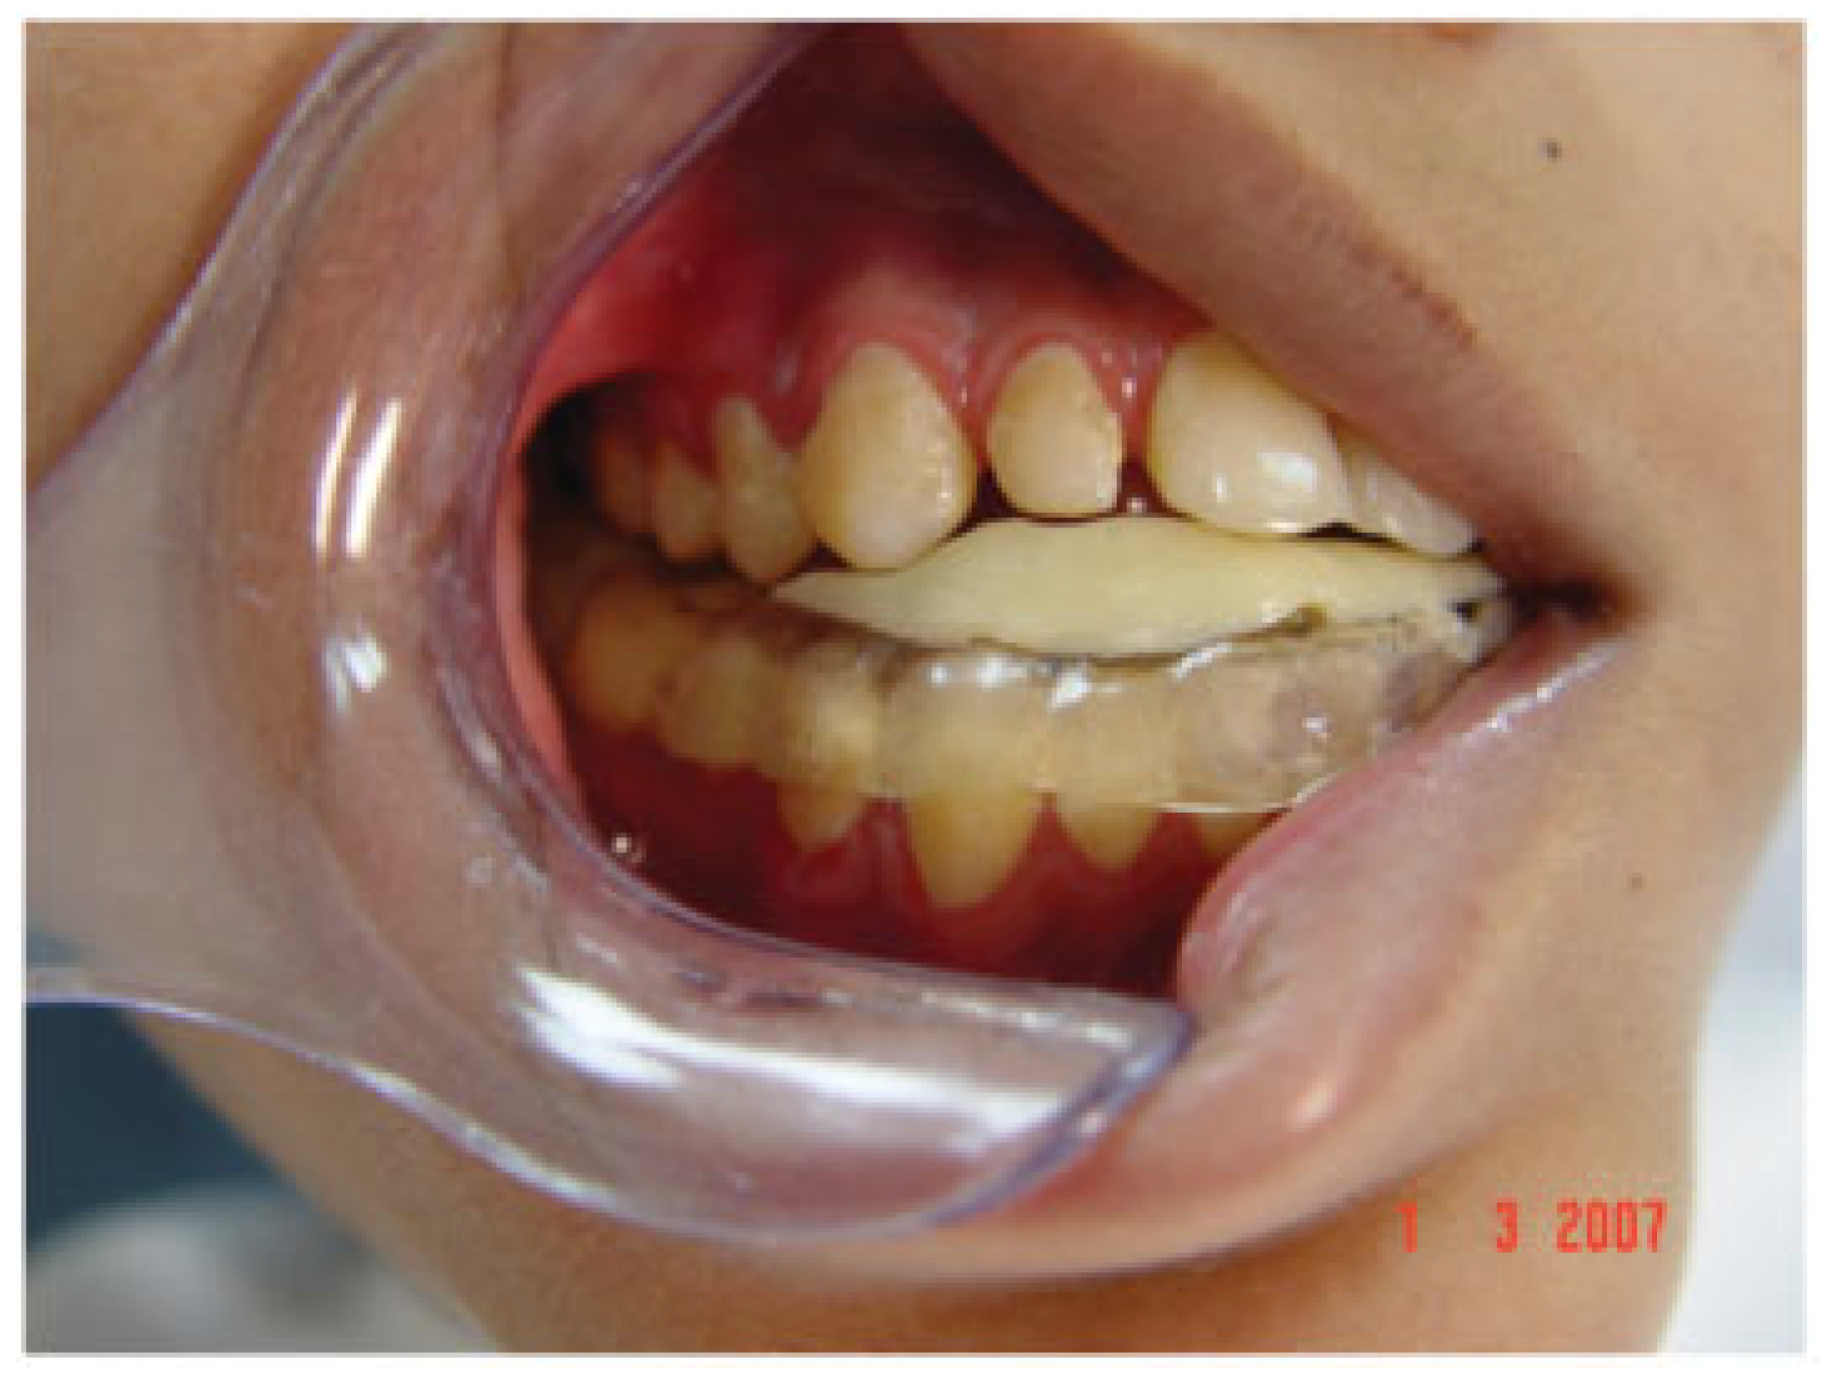

Figure 15. An acrylic plate was used to facilitate closure of the open bite. To achieve gradual closure of the open bite, the plate is trimmed in those areas that require the maxillary teeth to passively erupt.